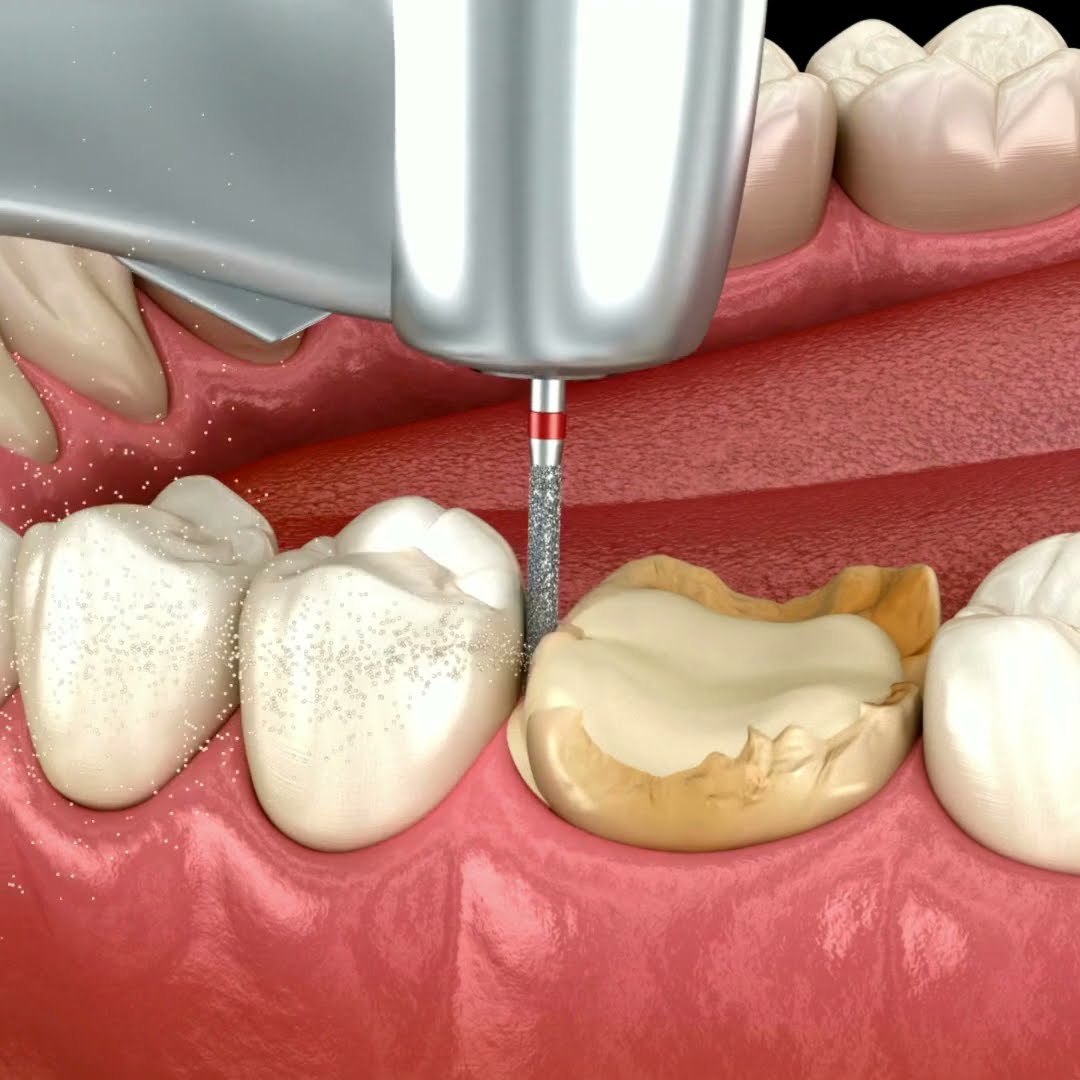

Клиническое применение

Препарирование зубов. Повышающий наконечник 1:5 помогает препарировать зуб быстрее и аккуратнее, чем с обычным высокоскоростным турбинным наконечником.

Удаление зубных протезов. Препарирование можно выполнить просто и легко даже на крепких протезах из таких материалов, как цирконий, амальгама, металлокерамика и т.д.

Край зубного протеза. Поскольку микромотор MicroNX EL-B40L вырабатывает высокую мощность даже на низкой скорости, поверхность препарирования зуба ровная, что позволяет изготовить оптимальный протез с точным формированием десневого края без грубых сколов.